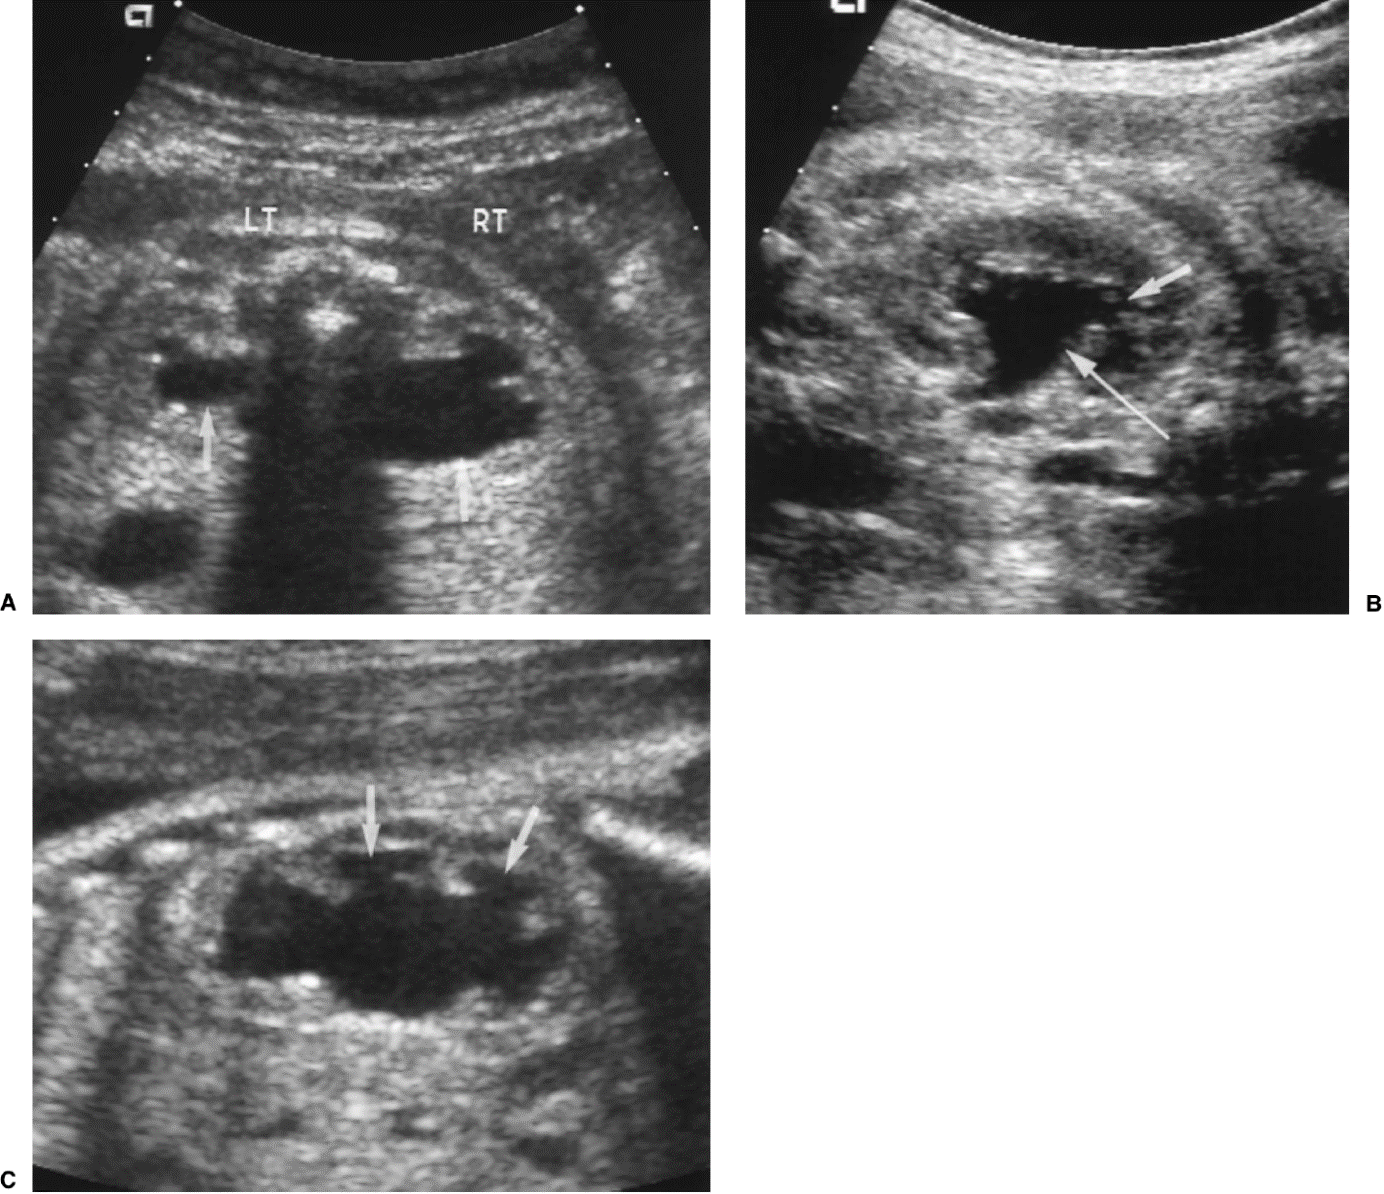

Normale plasbuis voorbij de kleppen

Plaats van de urethrakleppen

Verwijd eerste deel van de plasbuis tot aan de kleppen

Kleine, kramperige blaas met kartelige contour veroorzaakt door uitstulpingen van de blaaswand (divertikels)

Terugstroom van urine tot in de nier (vesico-ureterale reflux) en verwijde urineleider

Plasfoto met contrastmiddel (mictie cystogram)